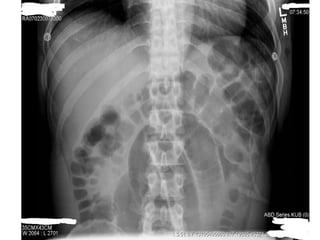

Investigations: • Radiographs areessential to confirm the diagnosis and accurate the site of the obstruction. • The radiological diagnosis is based on a supine(erect) abdominal radiograph. • If conditions of the patient are poor a lateral decubitus position view may be taken. • Usually can determine whether small bowel, colon or both are distended. • Radiographs show multiple gas-fluids levels, with distended bowell resembling an inverted U.

• 19.

• Obstruction ofthe small bowel outlines the valvulae conniventes, which occupy the entire transverse diameter of the bowel image. • Small bowel pattern occupies the more central portions of the abdomen. • Large bowel obstruction shows haustral markings, that occupies only a portion of the transverse diameter of the bowel, unlike valvulae conniventes, are spaced irregularly and the indentations are not placed opposite one another. • Large bowel pattern occupies the periphery or pelvis portion of the abdomen. • A distended caecum is shown by a rounded gas shadow in the right iliac fossa.

• 22.

• Large bowelobstruction with competent ileocecal valve show colon distention and little small bowel gas. • Large bowel obstruction with incompetent ileocecal valve shows small and large bowell distention and fluids levels. • Barium enema performed carefully may give the diagnosis of colonic obstruction. • At times is difficult to distinguish paralytic ileus from mechanical obstruction radiographically. • In paralytic ileus gaseous distention occurs uniformly in stomach, small bowel and colon. • In paralytic ileus gas-fluid levels may be seen. • Others investigations include: Serum electrolytes, Full hemogram, coagulation profile, renal function test, etc.